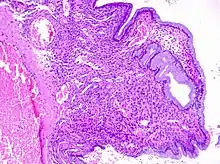

Histopathology of endocervical polyp: With endocervical epithelium and glands (mucinous columnar linings), edematous stroma and clear congestion. H&E stain.[1]